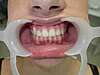

Supraclusion

APRÈS